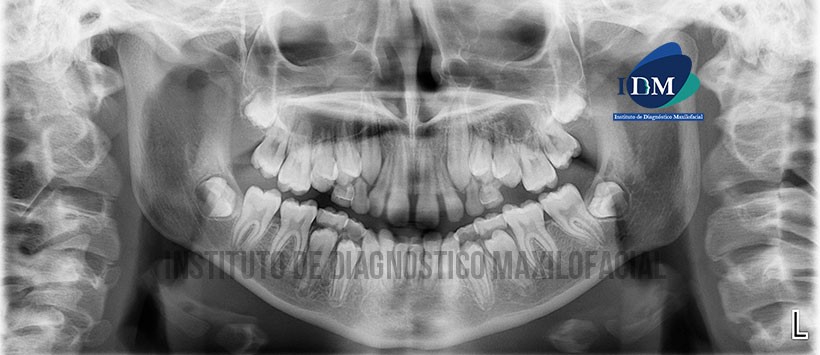

Paciente femenino de 12 años de edad, es referido al Instituto de Diagnóstico Maxilofacial (IDM) para evaluación tomográfica del macizo cráneo facial con motivos de ortodoncia y ortopedia maxilofacial.

En la radiografía panorámica (Figura 1) se observa opacificación de ambos senos maxilares, morfología y estructuras óseas de características aparentemente normales.